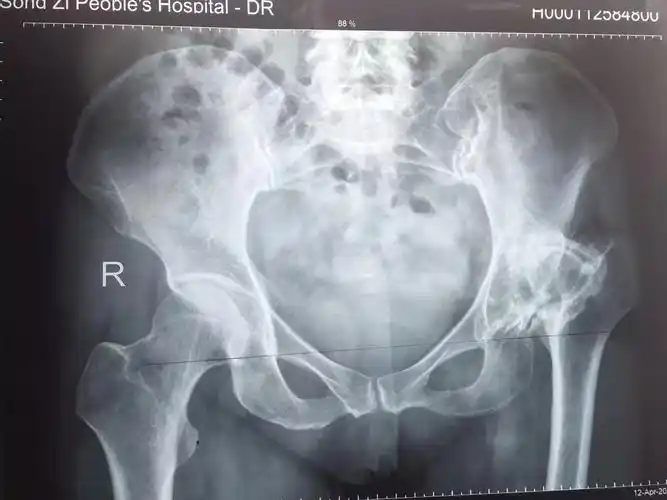

先天性髋关节发育不良

髋关节发育不良继发骨关节炎一例

发育性髋关节发育不良并髋关节骨性关节炎典型病例

先天性髋关节发育不良是指出生时髋关节发育不好,如髋臼发育太浅,髋臼